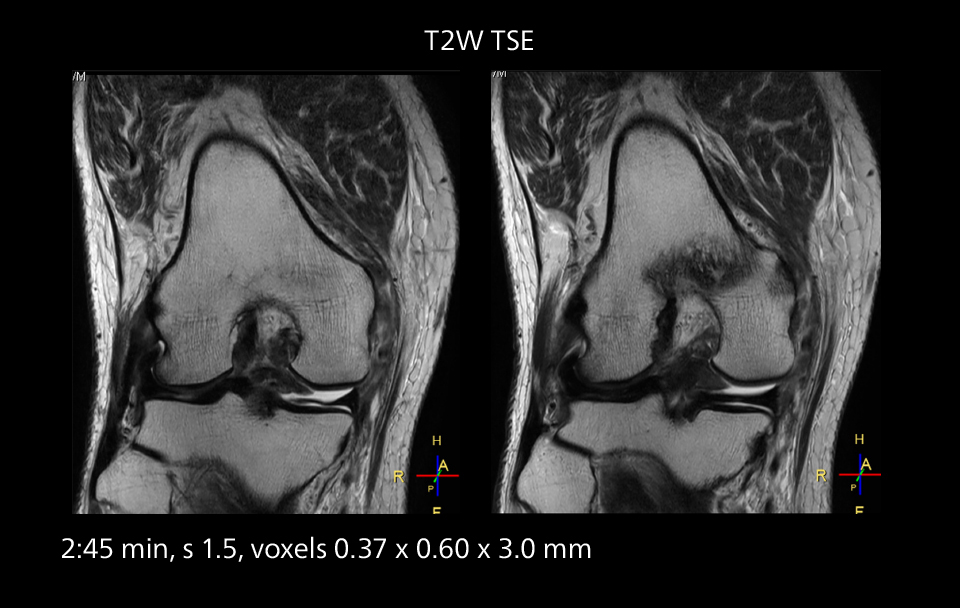

Images showing a posterior cruciate ligament (PCL) tear, a detached medial collateral ligament (MCL) on the tibial side and an intact anterior cruciate ligament (ACL). SmartPath to Elition X helped reduce scan time compared to previous imaging while maintaining resolution.

Overall, imaging time per sequence has been reduced since the Elition X upgrade. This can help reduce the risk of patient movement and the need for rescans. “As our hospital has many elderly patients, we consider it important to obtain high-quality data in a short time,” Dr. Makuuchi says. “Shorter imaging times are also useful for accepting emergency patients, because faster emergency studies have a reduced impact on the daily examinations schedule. In emergency cases it is also important that high quality images are obtained in a short time.”